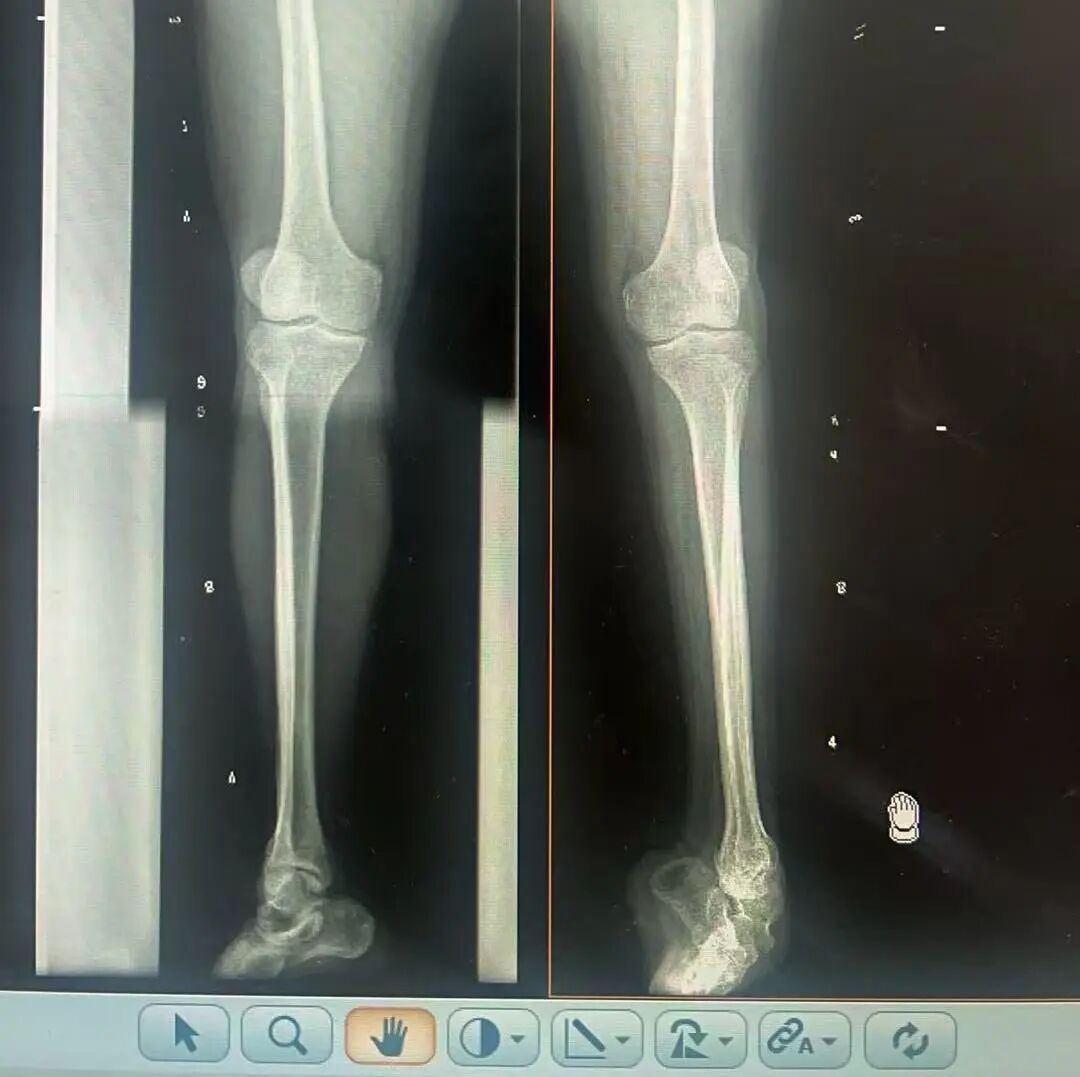

術(shù)前X光片 VS 術(shù)后治療效果

三十八年前,一紙“脊髓灰質(zhì)炎”的診斷,讓陽先生的人生染上了陰霾。闖過了急性期的鬼門關(guān),但后遺癥——嚴(yán)重的左踝馬蹄內(nèi)翻足畸形,是一道無形的枷鎖,禁錮著他的成長與自由。骨盆傾斜、雙腿不等長、左腳嚴(yán)重內(nèi)翻,他成長成人中行走的每一步,都伴隨著難以言說的艱辛。

骨科隨即為陽先生進(jìn)行了全面的檢查。診斷明確而復(fù)雜:陽先生患有脊髓灰質(zhì)炎后遺癥、左踝馬蹄內(nèi)翻足、骨盆傾斜……面對這張沉甸甸的診斷書,由肢體功能重建顯微修復(fù)學(xué)科組長鄭群龍所帶領(lǐng)的醫(yī)療團(tuán)隊(duì)沒有畏懼,“這是一個家庭38年的堅(jiān)守與期盼,我們必須全力以赴”

針對陽先生的復(fù)雜情況,鄭群龍醫(yī)師團(tuán)隊(duì)制定了詳盡的手術(shù)方案:左踝關(guān)節(jié)融合+馬蹄足畸形矯正+跟腱延長+外固定架固定術(shù)。手術(shù)的核心,正是伊里扎洛夫技術(shù)。這項(xiàng)技術(shù)如同精密的“時空建筑學(xué)”,通過微創(chuàng)安裝環(huán)形外固定架,前足-后足安裝鋼環(huán),再將足的鋼環(huán)與脛骨的固定鋼環(huán)在踝關(guān)節(jié)前、后、左、右用帶關(guān)節(jié)的螺紋桿連接,由此構(gòu)建成一個能體外牽拉調(diào)控的三維立體構(gòu)型,在術(shù)后進(jìn)行精準(zhǔn)、緩慢的調(diào)整,一寸一寸逐步將畸形的骨骼、軟組織恢復(fù)到正常位置。